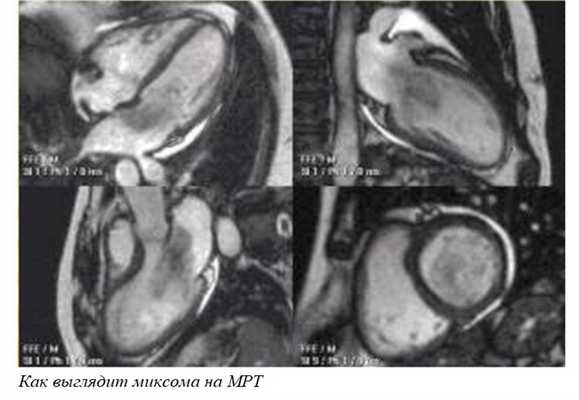

- Компьютерная или магнитно-резонансная томография (КТ, МРТ) - это дополнительные исследования. Их я назначаю при неясной УЗИ-картине, или чтобы лучше оценить объем разрастания опухоли.

- МРТ сердца. Магнитно-резонансная томография — «золотой стандарт» для диагностики апикальных опухолей. Исследование дополняется применением радиоактивных меток и контрастированием, чтобы четко разграничить здоровые и опухолевые ткани. Под контролем МРТ выполняется прицельная биопсия подозрительного новообразования.

МРТ также может использоваться в качестве дополнения к ЭХОКГ в случаях неоднозначных и противоречивых результатов. МРТ позволяет лучше локализировать опухоль и может быть полезна в случае хирургической резекции. Также данная методика обеспечивает более надежную оценку систолической функции желудочков